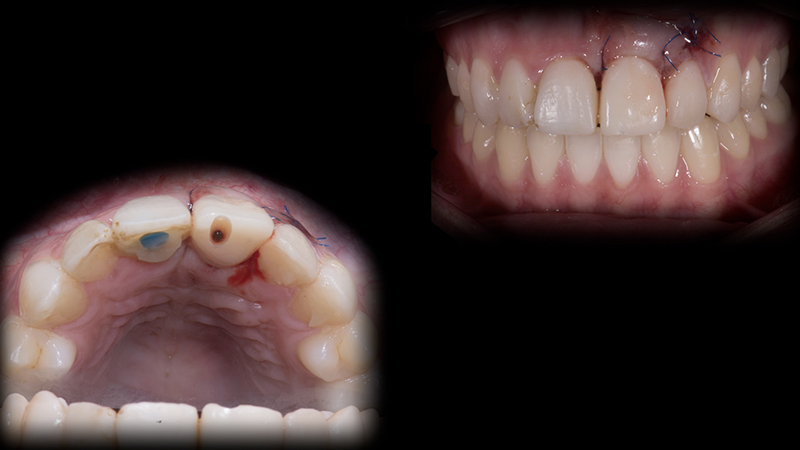

Per un trauma frontale, una paziente di 24 anni con sorriso gengivale, perde il dente 2.1. Il dente 1.1 è dislocato palatalmente e il dente 1.2 presenta un danno al margine incisale (Fig. 2a, Fig. 2b). La CBCT mostra una frattura in entrambe le placche vestibolari ossee, in corrispondenza dei due incisivi centrali superiori (Fig. 3).

Fig. 2a - Stato iniziale.

Fig. 2b - Stato iniziale intraorale.

Terapia immediata

Ho visitato la paziente per la prima volta a tre giorni dal trauma e non è stato possibile reimpiantare il dente 2.1.  A supporto temporaneo di papille e margine gengivale di quest'area, ho rimosso la radice del dente avulso, modificato il terzo cervicale della corona con del composito e cementato il dente avulso ai denti adiacenti con filo metallico e composito (Fig. 4).

Soluzione d'emergenza

Fig. 4 - Soluzione d'emergenza.